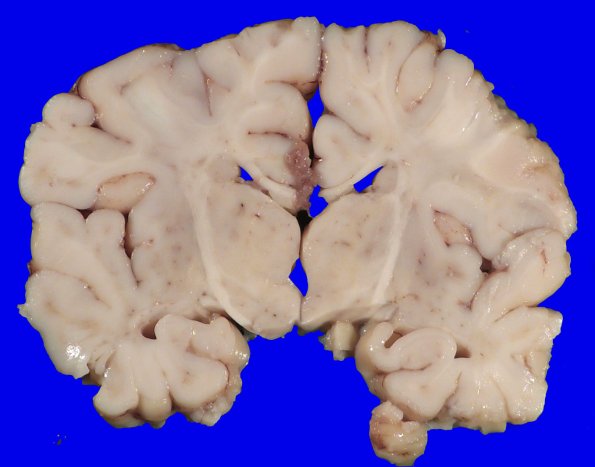

Coronal sections of the fixed brain show well preserved cortex and deep gray with a hint of white matter discoloration.